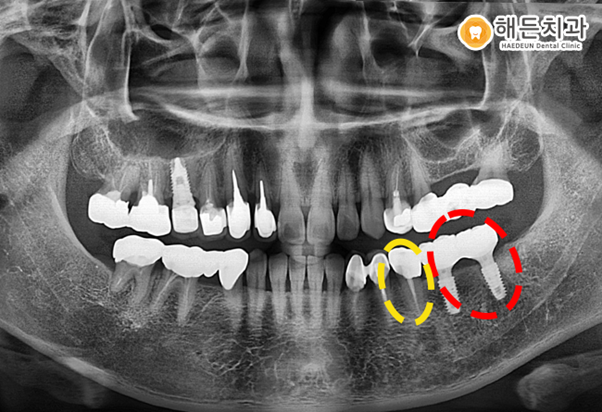

작은 어금니는 신경치료 후 크라운을 덮어 씌워 마무리를 해주었습니다.

임플란트 부위는 3~4개월 충분히 기다린 후 머리 역할을 하는 보철물을 덮어 씌워 주었습니다.

환자분께서 진료에 잘 협조해 주셔서 임플란트 및 크라운 치료를 무사히 마칠 수 있었습니다.

이렇게 치료를 마무리 한 후 6개월 정도 지나서 본원을 내원하셨는데요.

오른쪽 앞니가 갑자기 음식을 먹고 나서 통증이 심하다고 내원하셨습니다.

확인을 해보니 치아의 동요도가 3단계로 매우 많이 흔들리고 있었습니다.

3단계 동요도는 치아가 좌우로 뿐만 아니라 수직으로도 흔들리는 경우를 말합니다.

.

치아의 뿌리 끝을 절제해 치료하는 치근단 절제술을 시행해 볼 수는 있었으나

치아의 동요도가 너무 심해 환자분과 상의 후 발치를 결정했습니다.

발치 후 임플란트까지 잘 마무리 된 아산시임플란트잘하는곳 해든치과에서의 치료 후 모습입니다.

추후 정기적인 치과 검진을 하며 관리해드리기로 했습니다. ^^